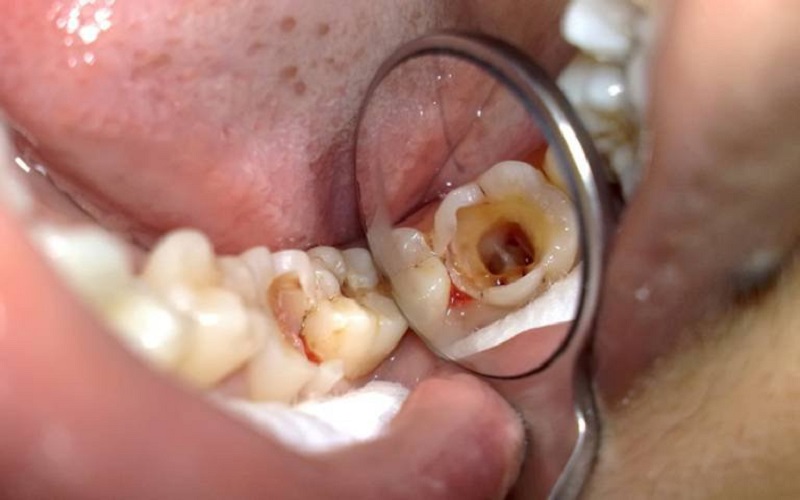

- Sâu răng.

- Bước 1: Khám tổng quát tình trạng răng miệng và điều trị cần thiết trước khi thực hiện trám răng.

- Bước 2: Bác sĩ sẽ tiến hành vệ sinh, sát trùng, sát khuẩn răng miệng, đặc biệt là vị trí trám răng

- Bước 3: Đưa chất gắn trám lên răng sau đó tạo hình chất trám vừa khít với vết răng hỏng, giống răng thật và thẩm mỹ.

- Bước 4: Sau khi tạo hình, bác sĩ sẽ dùng đèn chiếu laser trong 30-45 giây, kích hoạt chất trám giúp gắn chặt với răng bền vững.